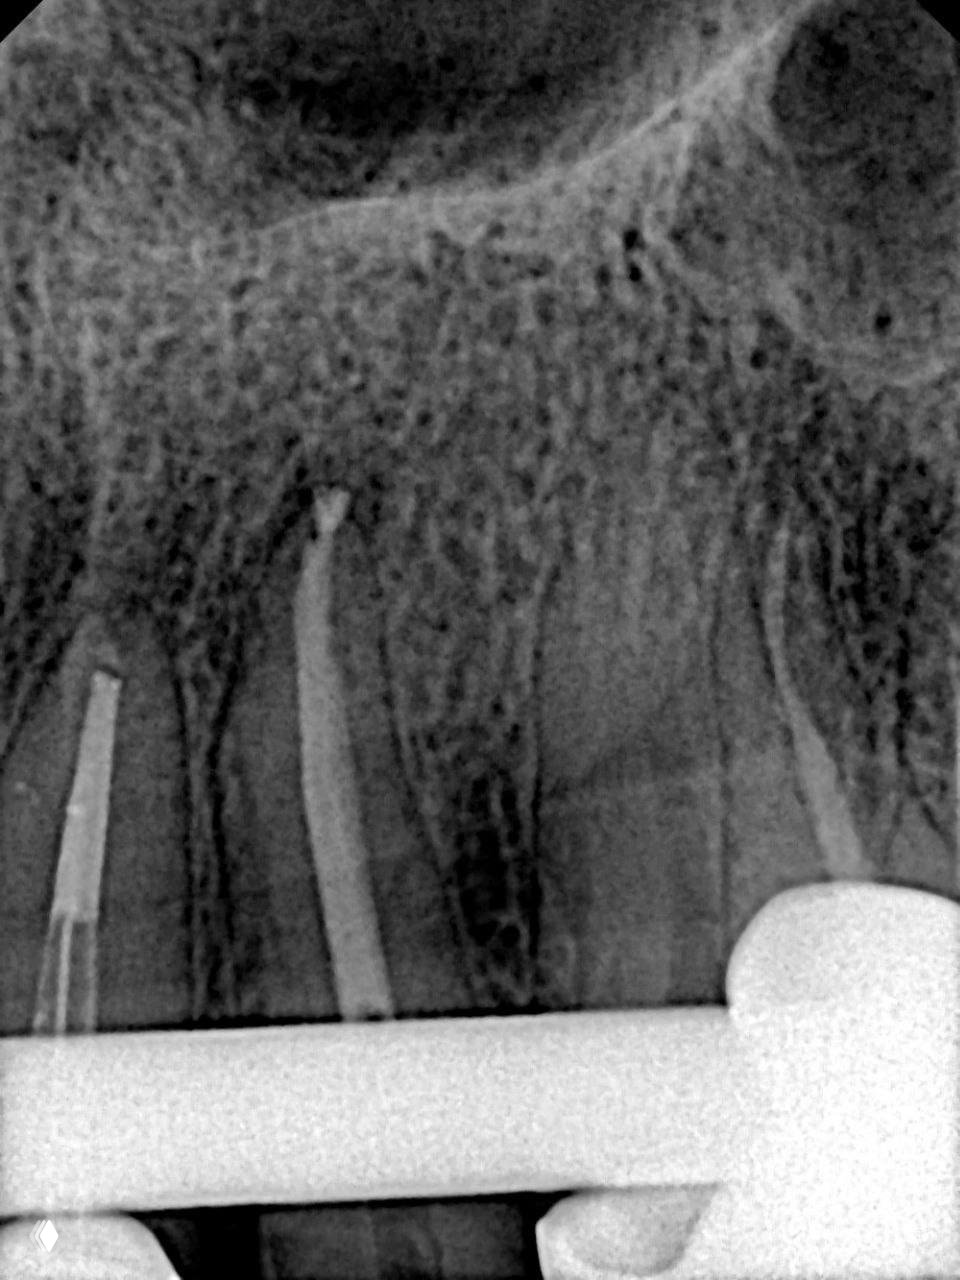

Что делать, если сидишь себе работаешь уверенно, и тут бац 💥 обломок файла или эндочака сломался в апикальной части.

Спокойно, друзья, сейчас расскажу, как я справилась с этой ситуацией в реальном клиническом случае, и вы увидите, что это совсем не приговор для зуба и не повод для паники 🙌

Я начала с ручных К-файлов, прошла последовательно от 10 до 20, аккуратно, без спешки 🎯 Затем перешла на машинные Eighteeth Blue в последовательности 15.04, 20.04, 25.04, 30.04, и вот тут уже открывается пространство для маневра.

🔹 Сценарий второй: обломок не видно или страшно его протолкнуть глубже

Тут мы продолжаем байпас машинными файлами до 35.04, а потом берём 25.04 и запускаем его на моторе против часовой стрелки, и он как маленький помощник вытягивает обломок наверх 🪄